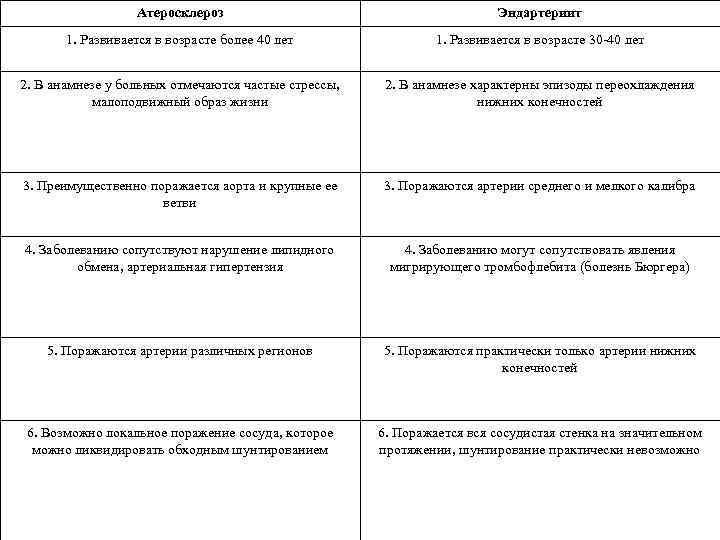

Атеросклероз Эндартериит 1. Развивается в возрасте более 40 лет 1. Развивается в возрасте 30 -40 лет 2. В анамнезе у больных отмечаются частые стрессы, малоподвижный образ жизни 2. В анамнезе характерны эпизоды переохлаждения нижних конечностей 3. Преимущественно поражается аорта и крупные ее ветви 3. Поражаются артерии среднего и мелкого калибра 4. Заболеванию сопутствуют нарушение липидного обмена, артериальная гипертензия 4. Заболеванию могут сопутствовать явления мигрирующего тромбофлебита (болезнь Бюргера) 5. Поражаются артерии различных регионов 5. Поражаются практически только артерии нижних конечностей 6. Возможно локальное поражение сосуда, которое можно ликвидировать обходным шунтированием 6. Поражается вся сосудистая стенка на значительном протяжении, шунтирование практически невозможно 63